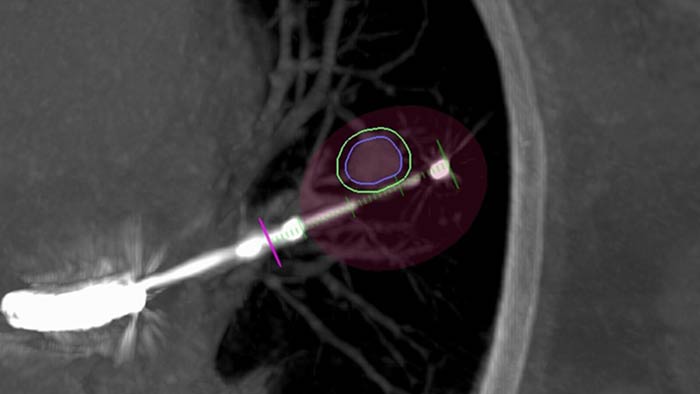

Planning and guidance for percutaneous biopsy, marking and ablative therapy.

with tumor segmentation, 3D navigation support for endobronchial procedures.